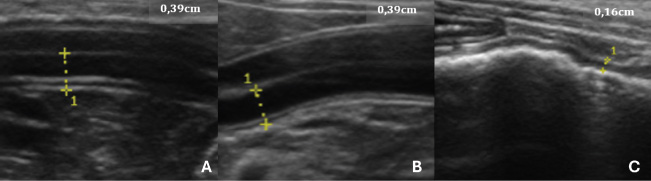

In relation to the USG of the intestines (Fig. 1) of the animals in this group, all the segments were assessed and measured, which determined the criteria for assessing the thickness of the organ wall, which varied according to the age group and the weight or body condition of the animal, considering the influence of thickness based on the development of the organism.

Fig. 1. USG images of the intestines of G1 dogs (asymptomatic without intestinal thickening). A, duodenum; B, jejunum; C, descending colon. The yellow dashed lines between the crosses indicate the measurements, and the values are shown in the top right-hand corner of each image.